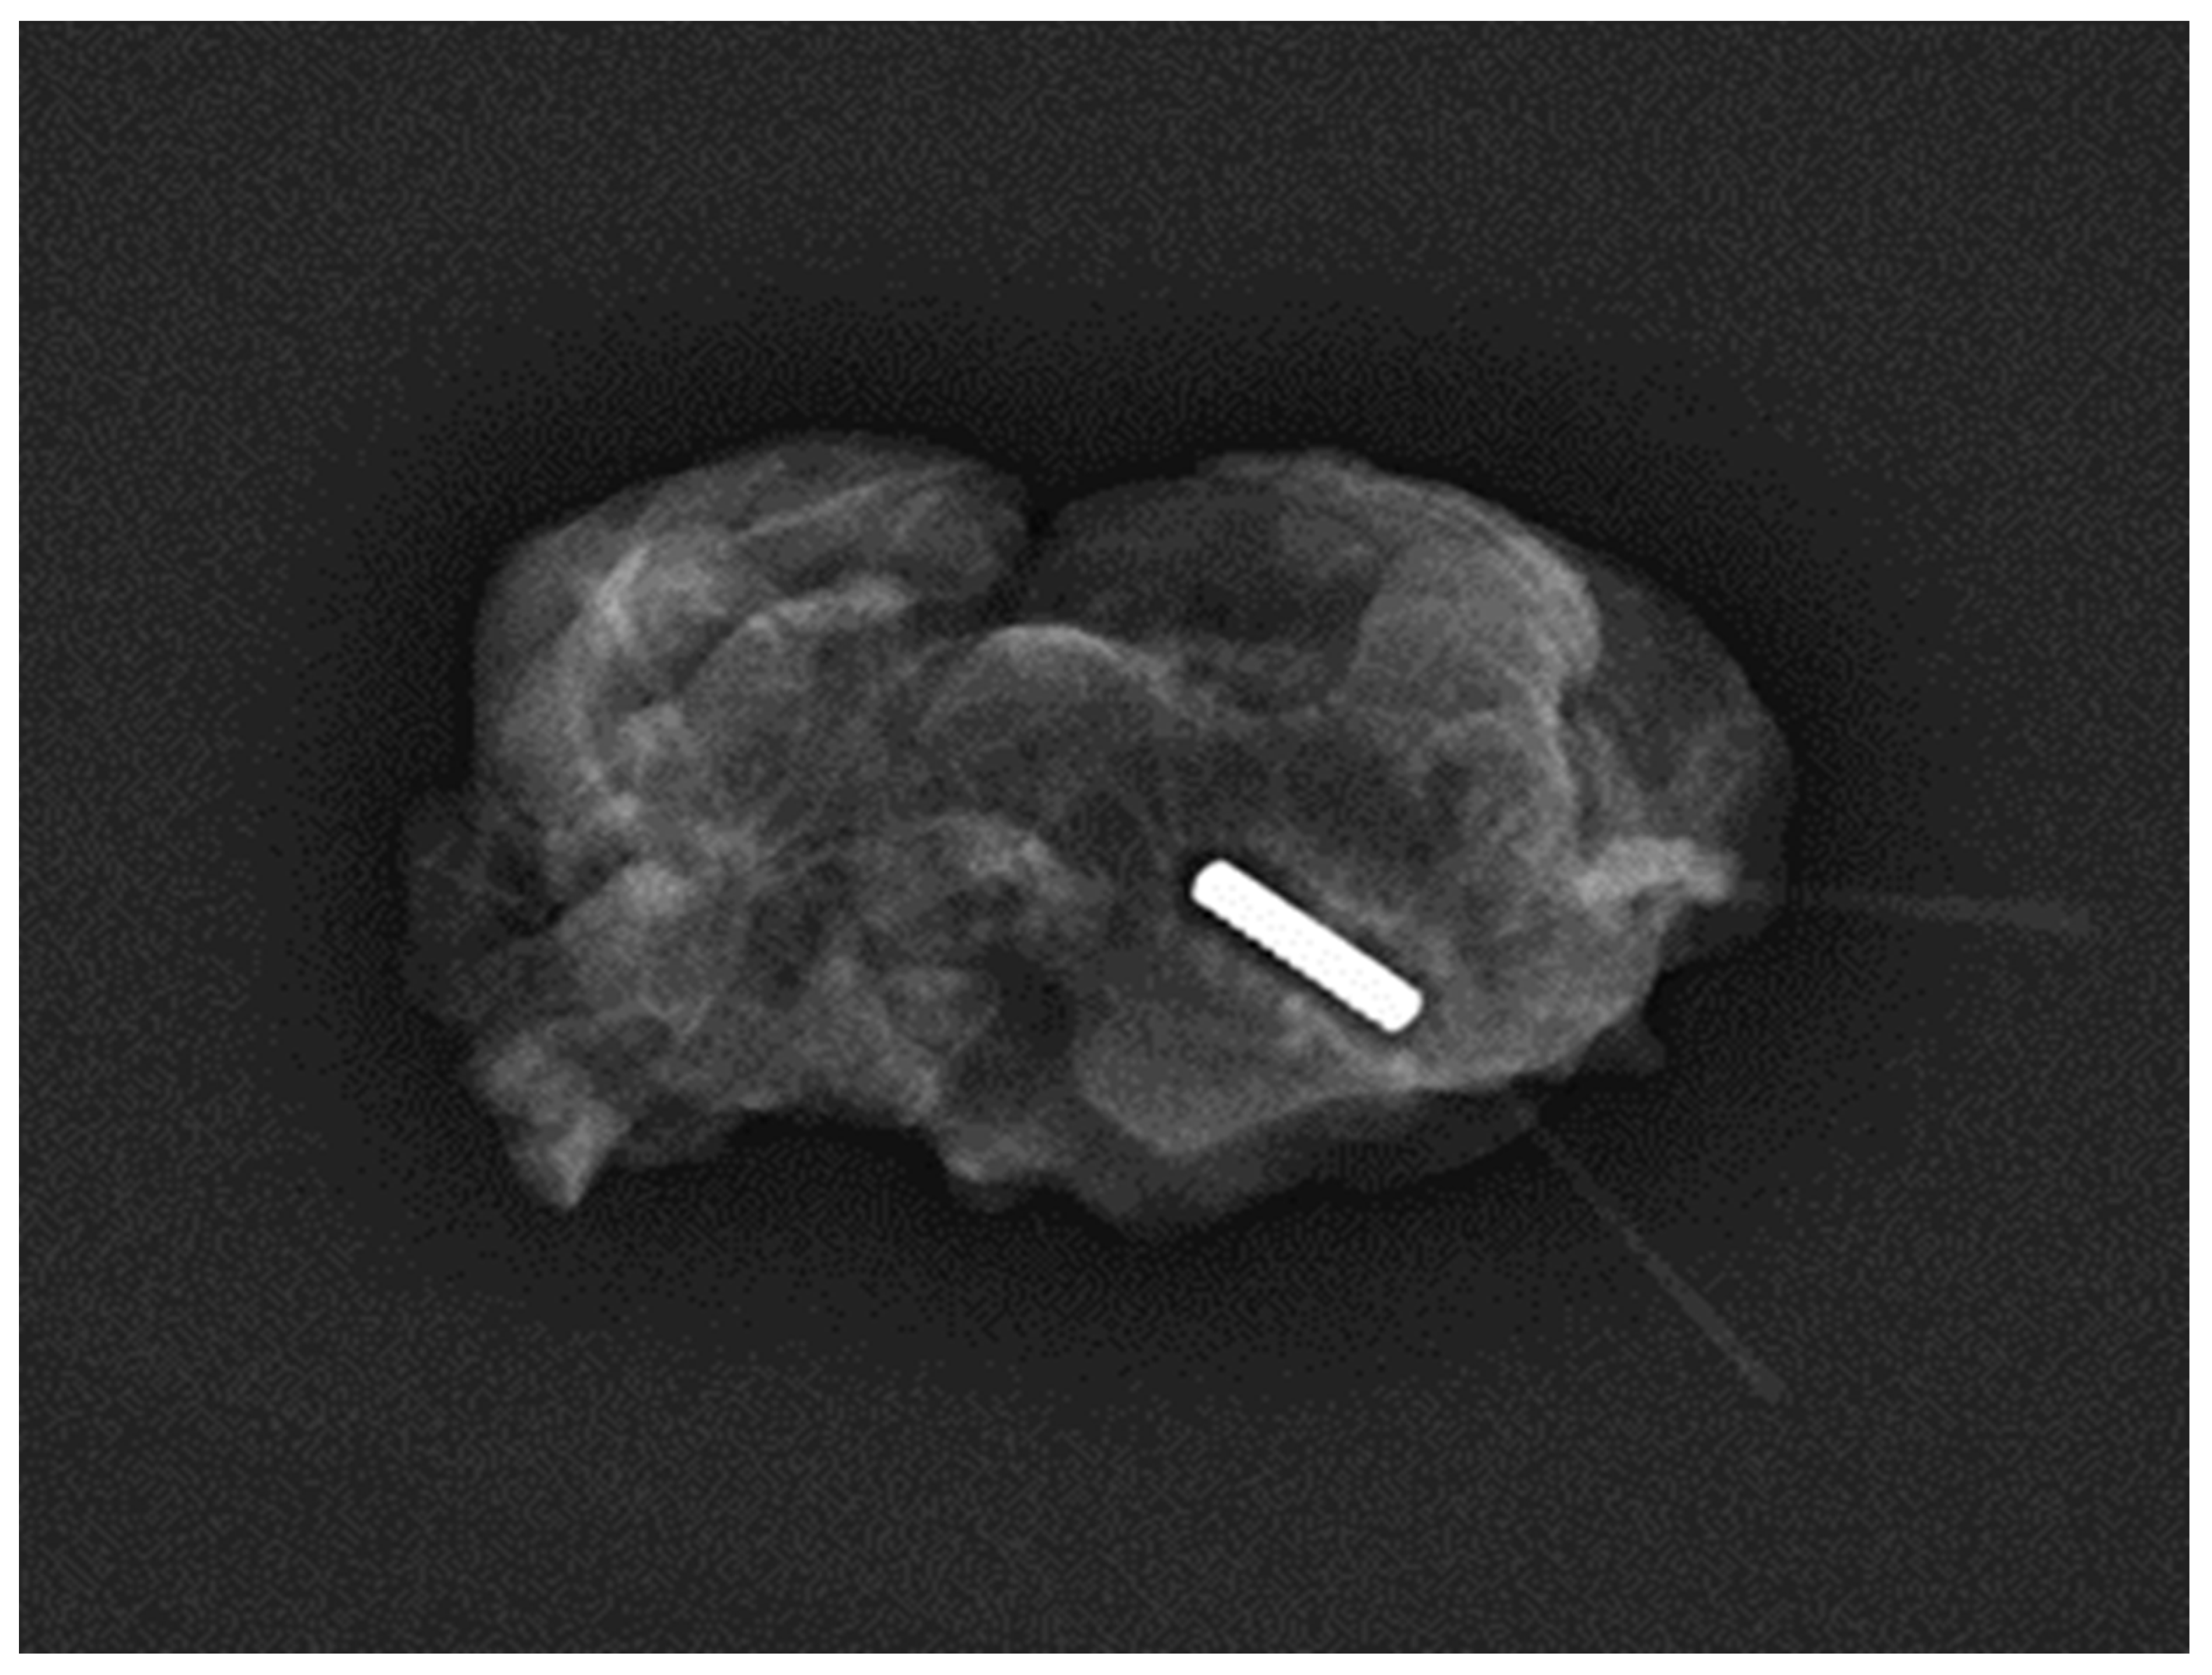

Magseed® technology, introduced into clinical practice in 2016, has undergone improvements to enhance user-friendliness and MRI compatibility, expanding its utility [22]. Initially utilised primarily for non-palpable breast lesions [23], its acceptance for axillary applications has gradually increased. However, there remains limited literature on its efficacy in aiding TAD. Our analysis, encompassing 494 Magseed® TAD procedures, provides evidence of its performance since the publication of the first study by Greenwood et al. in 2019. The 100% successful deployment rate is facilitated by the small size of the seed (5 × 1 mm) and narrow bore of the introducer needle (18 gauge) [23] (Figure 3).

Figure 3. Specimen radiograph of a magnetic seed containing a lymph node harvested during TAD in a 65-year-old patient who received NST after the deployment of the seed (Magseed®).